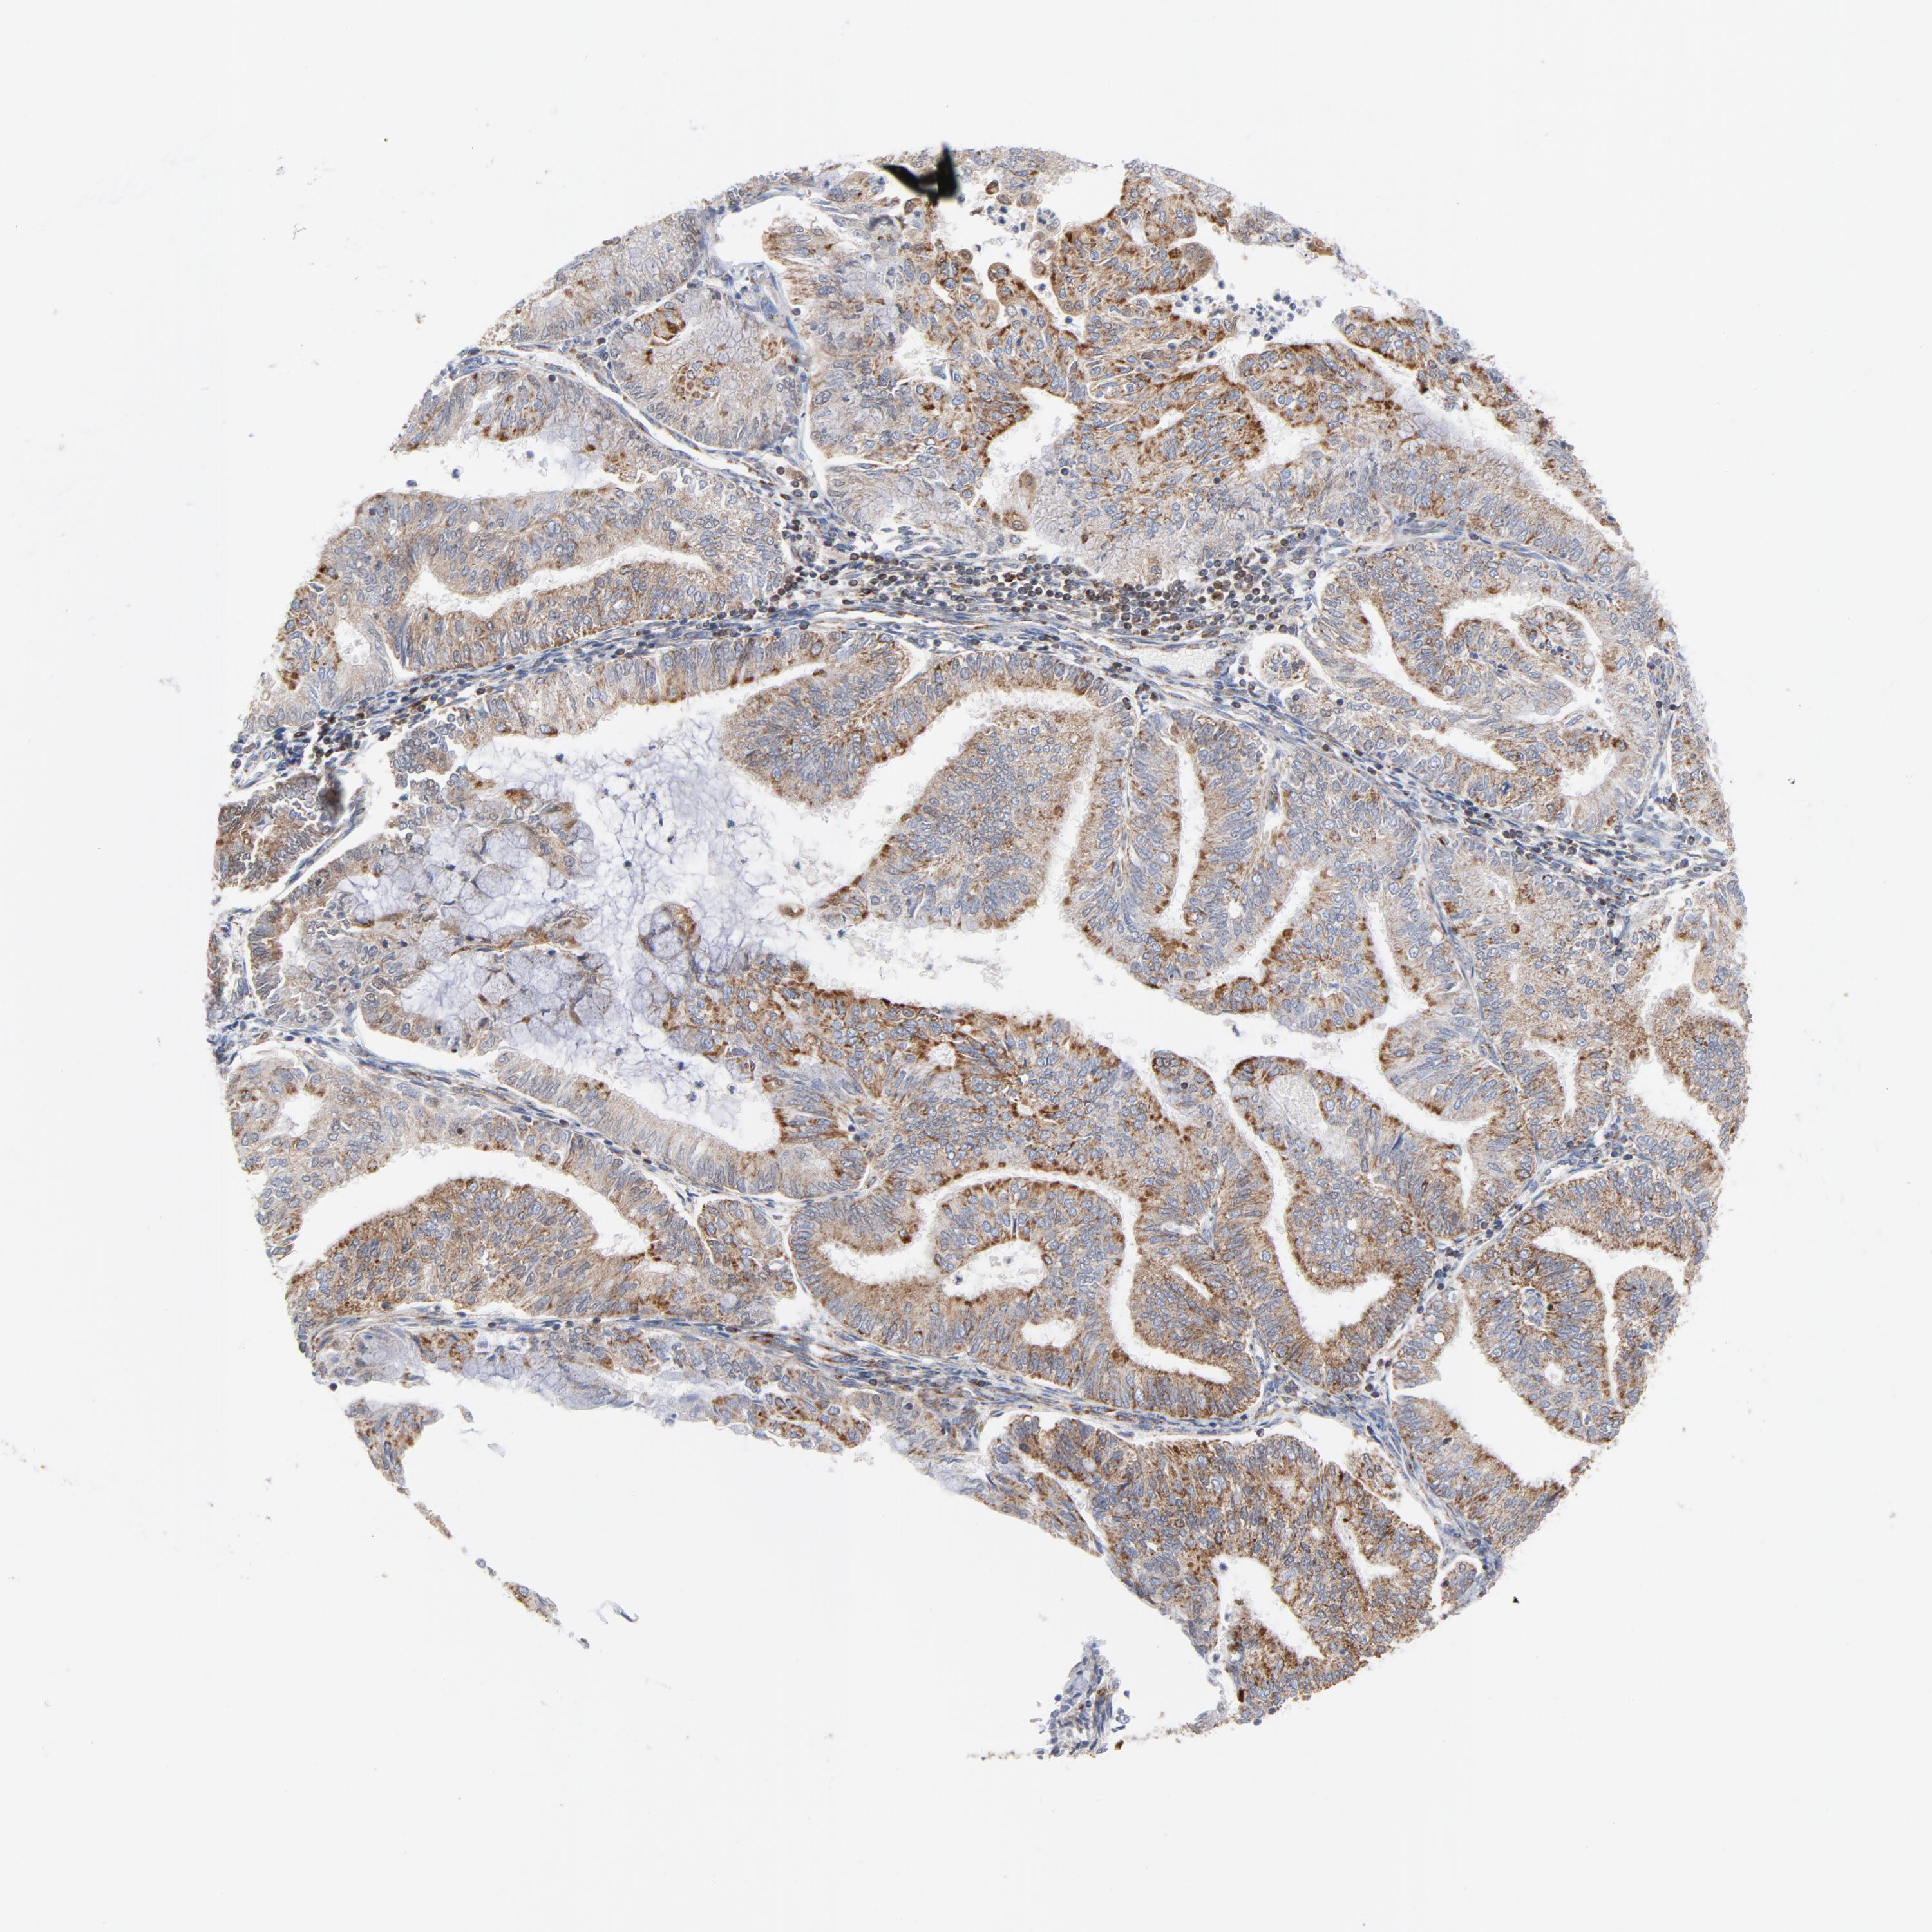

ENDOMETRIAL CANCER - Protein expressioni

A mouse-over function shows sample information and annotation data. Click on an image to view it in a full screen mode. Samples can be filtered based on level of antibody staining by selecting one or several of the following categories: high, medium, low and not detected. The assay and annotation is described here.

Note that samples used for immunohistochemistry by the Human Protein Atlas do not correspond to samples in the TCGA dataset.

Antibody stainingi

Antibody staining in the annotated cell types in the current human tissue is reported as not detected, low, medium, or high, based on conventional immunohistochemistry profiling in selected tissues. This score is based on the combination of the staining intensity and fraction of stained cells.

Each image is clickable and will lead to virtual microscopy that enables deeper exploration of all samples and also displays staining intensity scores, fraction scores and subcellular localization as well as patient and tissue information for each sample.

Antibody HPA001825

Antibody CAB003857

Staining

High

Medium

Low

Not detected

Intensity

Strong

Moderate

Weak

Negative

Quantity

>75%

75%-25%

<25%

None

Location

Nuclear

Cytoplasmic/membranous

Cytoplasmic/membranous,nuclear

Adenocarcinoma, NOS

Neoplasm, malignant, NOS